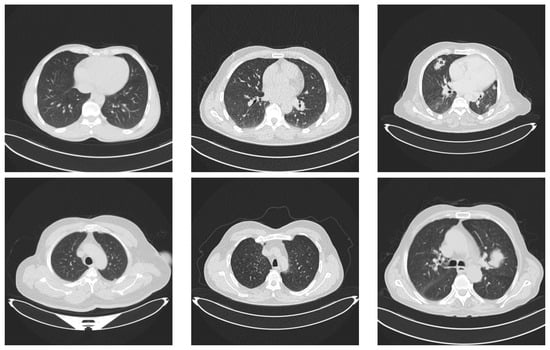

We selected a dataset from Kaggle [,] that includes CT scans of lung cancer and healthy lungs. The dataset has three classes: normal, benign, and malignant. Figure 2 depicts two examples of each class in the dataset.

Figure 2.

Examples of lung images. Images in the first column represent lungs with no tumors. The images in the middle column represent benign tumors and the last column contains two images with malignant tumors.

The images were in DICOM format and were preprocessed to anonymize patient identifiers. The dataset comprised 110 cases, varying in patient age, sex, residential area, and socioeconomic status, among other variables. It contained 1190 images, although we detected and removed duplicate files, with a total of 1054 unique images. These were distributed as shown in Table 1.